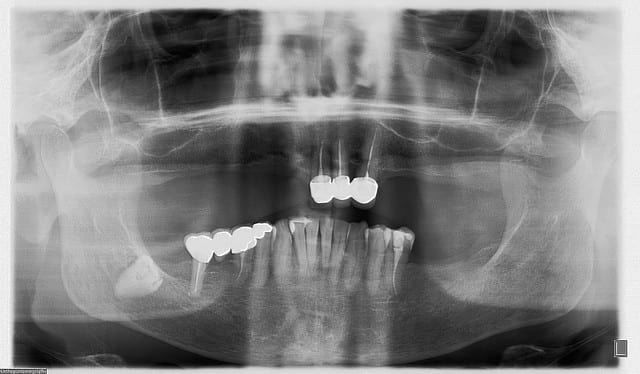

Eu pratiquant une mise en charge légèrement ou différée tu perds tous les avantages de la mise en charge immédiate. Le protocole de mise en charge immédiate POSITDENTAL est maintenant éprouvé, inévitablement il requiert une bonne maîtrise de l’implantologie. La passivité et précision du bridge se faont lors de la mise en place.

Vidéo d'une mise en charge immédiate: